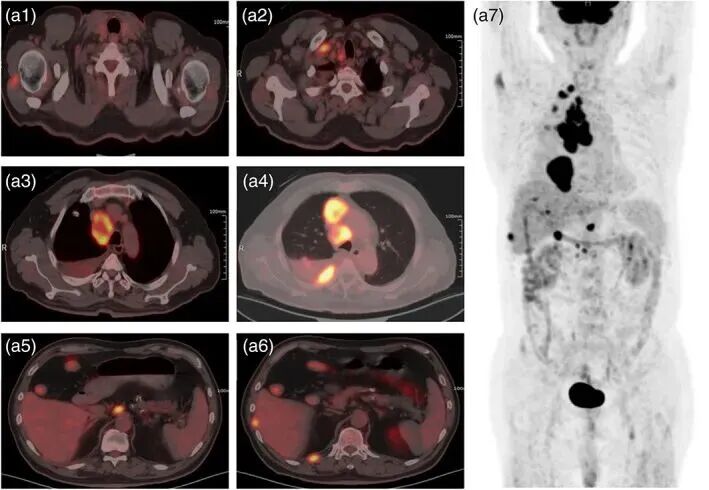

▲治疗前2022年5月拍摄的18F氟代脱氧葡萄糖正电子发射断层扫描/计算机断层扫描(18F-FDG PET/CT)图像

如果说体检结节让人困扰,那么真正确诊恶性病变时,患者更希望看到治疗曙光。2023年,《Thoracic Cancer》杂志刊登了天津医科大学肿瘤医院团队的一例临床案例。

患者是一位67岁女性,被确诊为广泛期小细胞肺癌,伴随多发肺结节。由于身体条件差,既无法耐受化疗,也缺乏标准治疗方案。科研团队为其设计了个性化免疫治疗方案:

来自健康供体的PD-L1增强型异体NK细胞,每两周输注一次;联合血管生成抑制剂安罗替尼;配合免疫检查点抑制剂Atezolizumab。

▲治疗5个月后,18F-脱氧葡萄糖正电子发射断层扫描/计算机断层扫描(18F-FDG PET-CT)图像的对比

令人震撼的是:三个月后,影像学复查显示,她肺部原本密布的亮点(结节及转移灶)大面积缩小甚至消退。医生团队在论文中写道,这一结果提示NK细胞有望在难治性肺癌患者中提供全新选择。